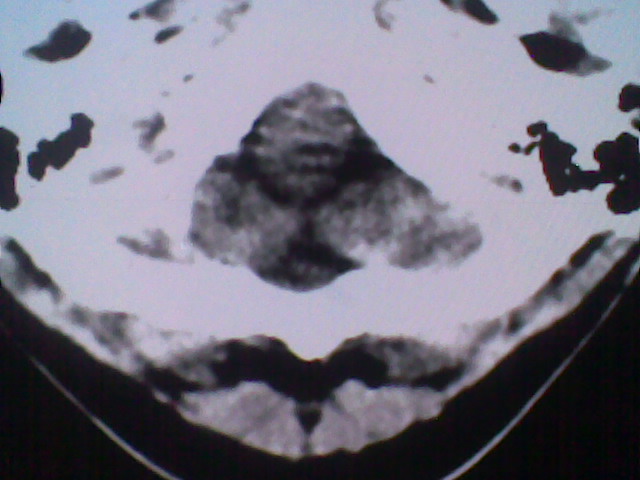

患者,男,头晕4天来诊,要求ct。

大枕大池合并蛛网膜囊肿。

支持 大枕大池合并蛛网膜囊肿。

考虑大枕大池合并蛛网膜囊肿。

有没有dandy-walker综合征的可能?